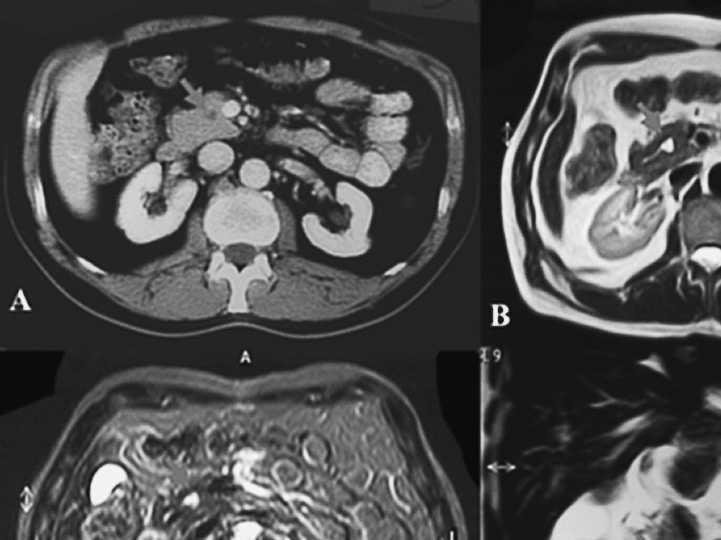

Varón de 59 años, intervenido 3 años antes de cáncer de colon en estadio B1 de Dukes. Al mes de una revisión completa normal, comenzó con molestias epigástricas, que ceden con la ingesta, y melenas. En la exploración destacaba palidez mucocutánea, heces melénicas, hemoglobina de 9,5 g/dl y CEA de 7,29 ng/ml. En panendoscopia oral se observó, en bulbo duodenal, ulcus de 1 cm con vaso sangrante que se esclerosa, cediendo la hemorragia. A los 6 días recidivó la hemorragia, que se controla con nueva esclerosis, esta vez de una masa ulcerada, que en la biopsia se informó como carcinoma pobremente diferenciado. Durante el ingreso se observó aumento progresivo de las concentraciones de transaminasas y bilirrubina total, con aparición de ictericia mucocutánea. Mediante ecografía se observó dilatación de la vía biliar intrahepática y extrahepática y ecos heterogéneos en la cabeza pancreática. Una tomografía computarizada (TC) abdominal mostró una masa en cabeza pancreática de 7 cm con infiltración de pared de la segunda porción de duodeno y adenopatías mesentéricas y celíacas (fig. 1). A las 2 semanas el CEA era de 32,13 ng/ml, el CA 125 de 193,8 U/ml y el CA 19.9 de 7.865 U/ml. Mediante laparotomía se observó una gran masa en cabeza pancreática, ulcerada al duodeno, y abundantes adenopatías celíacas, mesentéricas y retroperitoneales. Se realizó duodenopancreatectomía cefálica paliativa, quedando adenopatías en territorio mesentérico y retroperitoneal. El diagnóstico anatomopatológico fue carcinoma adenoescamoso de páncreas perforado a duodeno. A los 5 meses de la cirugía el paciente continúa vivo y asintomático, sin haber presentado nuevos episodios de melenas.

Fig. 1. Imágenes de tomografía computarizada del caso 1. A: vía biliar intrahepática dilatada. B: colédoco distal dilatado. C: disminución de calibre de colédoco, atrapado por el tumor. D: tumor que infiltra el duodeno.